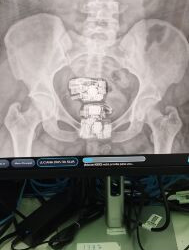

DivulgaçãoRaio X flagrou a visitante com vários materiais escondidos na região genital DivulgaçãoRaio X flagrou a visitante com vários materiais ...